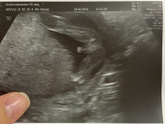

Швы на шейку

Девочки привет! Кому накладывали швы на шейку? Сколько вы времени в больнице пролежали после? Вроде такая манипуляция не хитрая... сделали бы и домой отпустили))) интересно сколько на самом деде длится все удовольствие? А то завтра ехать а на сколь дней … Читать далее